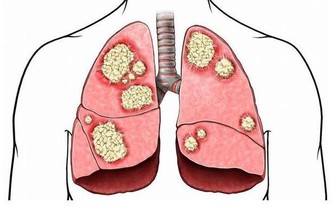

久之這些重金屬就會在腎小管內聚集,嚴重時甚至會引起腎小管的壞死。

我們吃下去之後,這些重金屬就會沉積在我們的腎小管內,久而久之,就會傷及我們的腎臟。